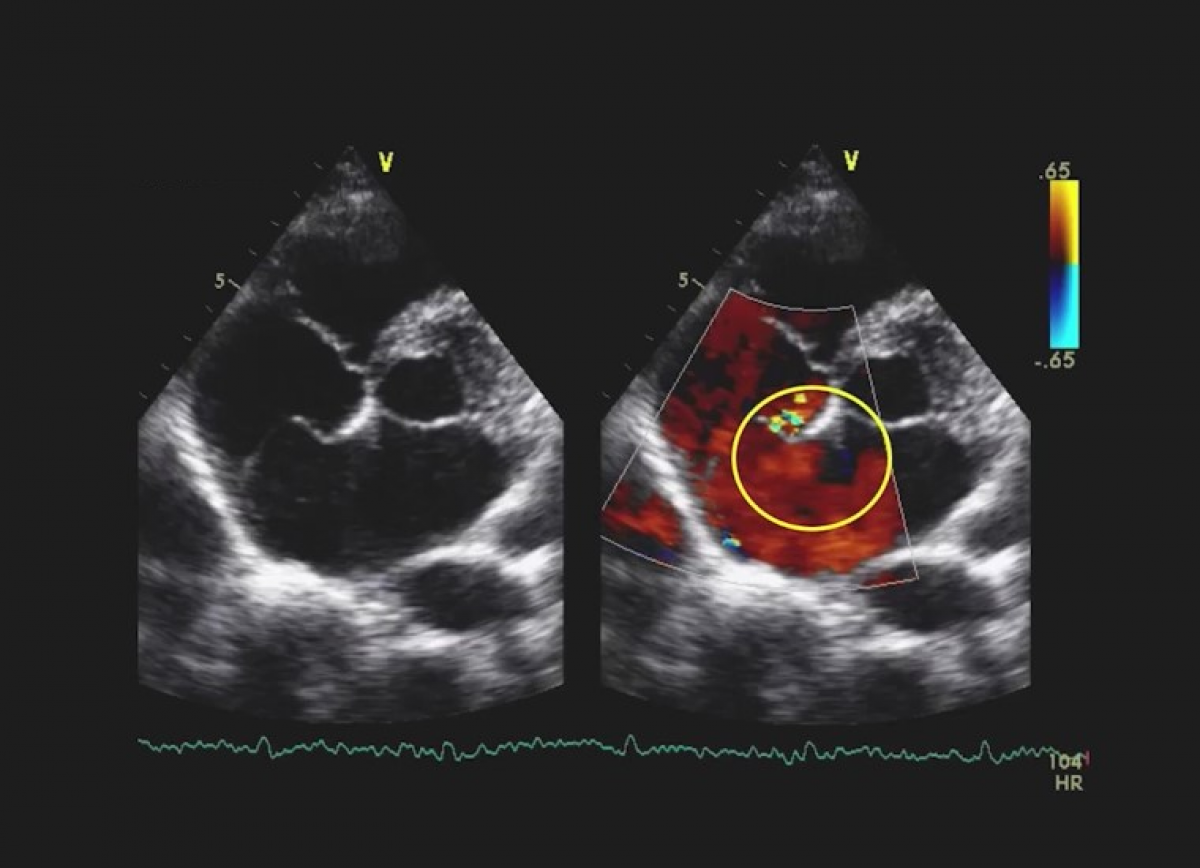

Pacjent z niewydolnością serca, ciężką niedomykalnością trójdzielną, przewlekłym zespołem wieńcowym, po przezskórnym zamknięciu uszka lewego przedsionka.

Ciężka niedomykalność mitralna i trójdzielna.

Ocena niedomykalności mitralnej.

Ocena niedomykalności trójdzielnej.

Kwalifikacja do przezskórnego leczenia niedomykalności mitralnej i trójdzielnej.

Ocena po przezskórnym leczeniu niedomykalności mitralnej i trójdzielnej.